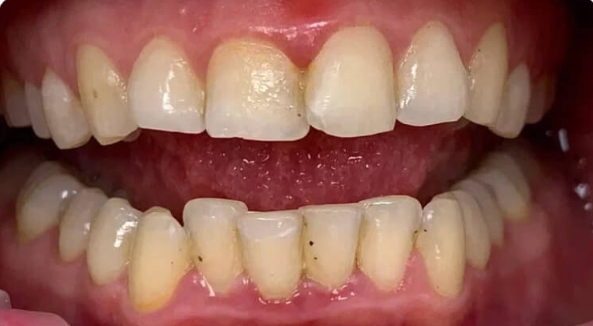

На странице представлено портфолио стоматологий Санкт-Петербурга с работами до и после профессиональной чистки зубов. В нашем портфолио собраны разные клинические случаи: от удаления незначительного налета до снятия массивного поддесневого камня. Здесь вы можете увидеть, как возвращается естественный цвет и внешний вид зубов после процедуры. Изучите результаты до и после чистки зубов, чтобы увидеть реальный эффект и выбрать клинику в Санкт-Петербурге, где профессиональная гигиена поможет вернуть зубам здоровый вид.

Профессиональная гигиена особенно важна при ортодонтическом лечении, ведь в повседневной жизни, дома, очень сложно поддерживать должный уровень гигиены полости рта! Даже если вы используете ирригатор и специальные ёршики! В нашей рубрике «до/после» вы видите то, что может быть с зубами при лечении брекетами, если не проводить своевременную чистку у врача-стоматолога. Марухно Дарья Александровна провела профессиональную чистку в несколько этапов, чтобы вернуть пациентке белизну ее собственных зубов! Брекет-система была поставлена не в нашей клинике, и почему пациентка не обратилась за профессиональной помощью раньше-вопрос) Но в данном случае, главное – итог! Кровоточивость после даже обычной чистки в такой клинической ситуации – естественный результат. Ведь обильный зубной налёт и зубной камень вызывают воспаление дёсен в виде гингивита, а порой даже пародонтита.